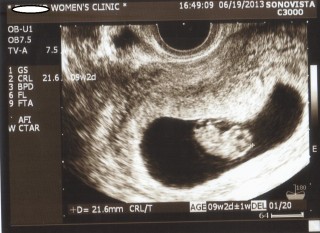

CRLは21.8mm(^ ^)

元気だよ!と言われ、ほっとしました。 9W2D、21.6mmでした。 2週間ぶりの検診だったのですが、ドキドキだったのですが元気で良かった☆ 母子手帳をもらうための書類もこの日にもらえました。